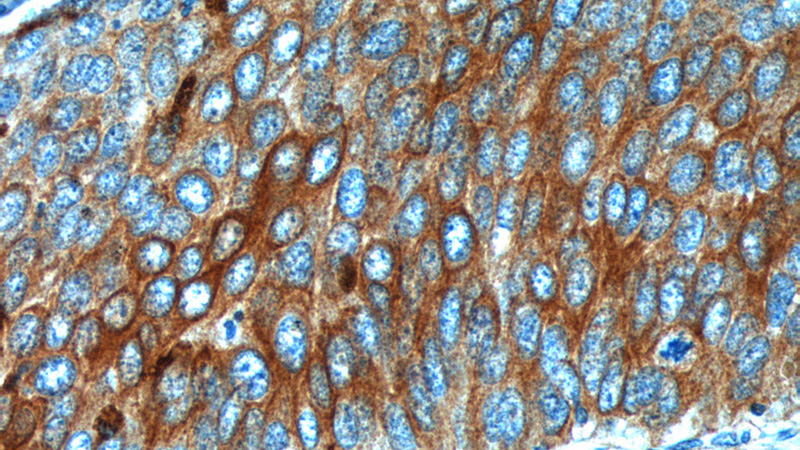

Expression of these cytokeratins is largely organ or tissue specific. The subsets of cytokeratins which an epithelial cell expresses depends mainly on the type of epithelium, the moment in the course of terminal differentiation and the stage of development. Thus a specific cytokeratin expression profile allows the identification of epithelial cells. Furthermore, this applies also to the malignant counterparts of the epithelia, (carcinomas), as the cytokeratin profile is generally retained. Thus the study of cytokeratin expression by immunohistochemistry techniques is a tool of immense value widely used for tumor diagnosis and characterization in surgical pathology.